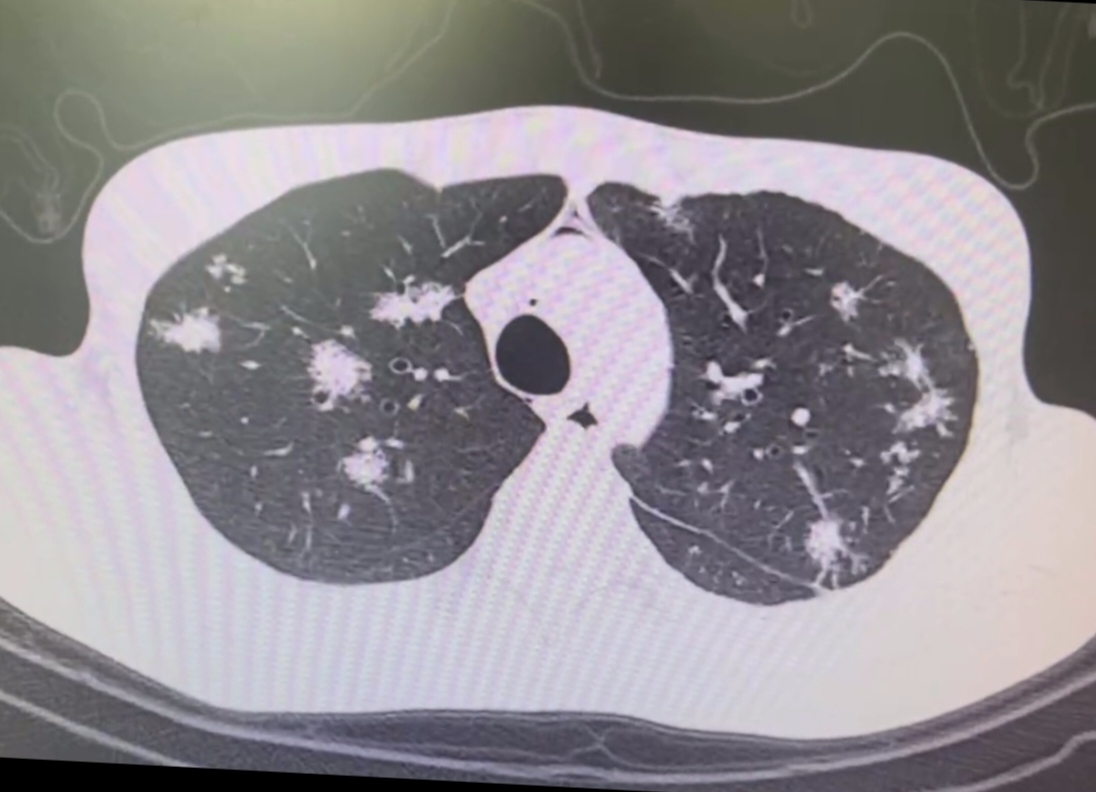

結核:神秘的粟粒妖怪

肺結核中的粟粒樣結核,就像一群神秘的粟粒妖怪,因為結核菌的感染,讓肺部布滿小結節。這種情況還伴隨著低熱、乏力等癥狀,就像被妖怪施了魔法一樣。雖然它不像大魔王那樣強大,但也不容小覷。就像孫悟空遇到的一些看似不起眼但卻十分難纏的妖怪,也需要認真對待。